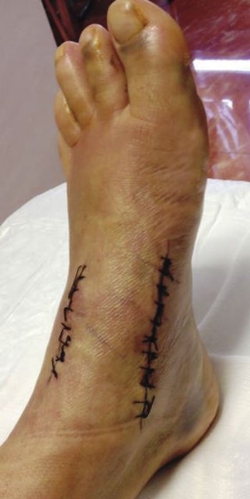

Al realizar la exploración física, se aprecia un ligero abultamiento en el borde interno del mediopié, doloroso sobre todo a la marcha (Figura 1).

Figura 1. Abultamiento en región medial del mediopié.